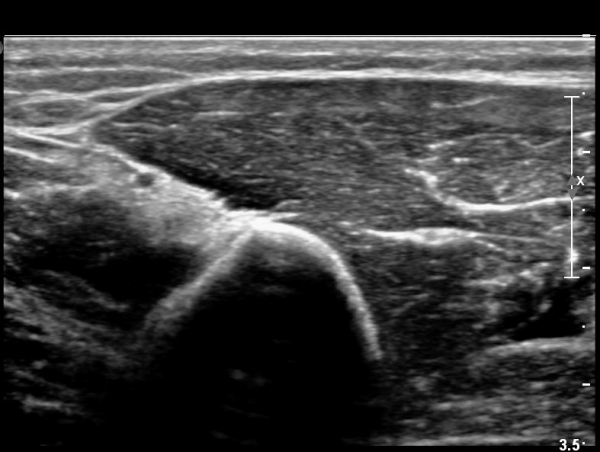

¿ä°ñ °í¶û ¸»´Ü¿¡¼ ¿ä°ñ½Å°æ Á¾´Ü¸é°Ë»ç»ó ¿ä°ñ½Å°æÀÇ Àú¿¡ÄÚ ºÎÁ¾°ú Áß°£ ºÎÀ§¿¡

±¹¼ÒÀû ÇùÂøÀÌ °üÂûµÈ´Ù(»çÁø 5).

¿ä°ñ °í¶û ±ÙÀ§ºÎ¿¡¼ ¿ä°ñ½Å°æ Ⱦ´Ü¸é°Ë»ç»ó ¿ä°ñ½Å°æÀÇ °æ¹ÌÇÑ Àú¿¡ÄÚ ºÎÁ¾ÀÌ °üÂûµÈ´Ù(»çÁø 6).

ŽÃÊÀÚ¸¦ Á¶±Ý ´õ ¸»´ÜÀ¸·Î À̵¿ÇÏ´Ï ¿ä°ñ½Å°æ Àú¿¡ÄÚ ºÎÁ¾ÀÌ ¶Ñ·ÈÇÏÁö ¾Ê´Ù(»çÁø 7).

¿ä°ñ °í¶û ±ÙÀ§ºÎ¿¡¼ ¿ä°ñ½Å°æ Á¾´Ü¸é°Ë»ç»ó ¿ä°ñ½Å°æÀÇ °æ¹ÌÇÑ Àú¿¡ÄÚ ºÎÁ¾°ú Áß°£ ºÎÀ§¿¡

¹Ì¼¼ÇÑ ±¹¼ÒÀû ÇùÂøÀÌ °üÂûµÈ´Ù(»çÁø 8)